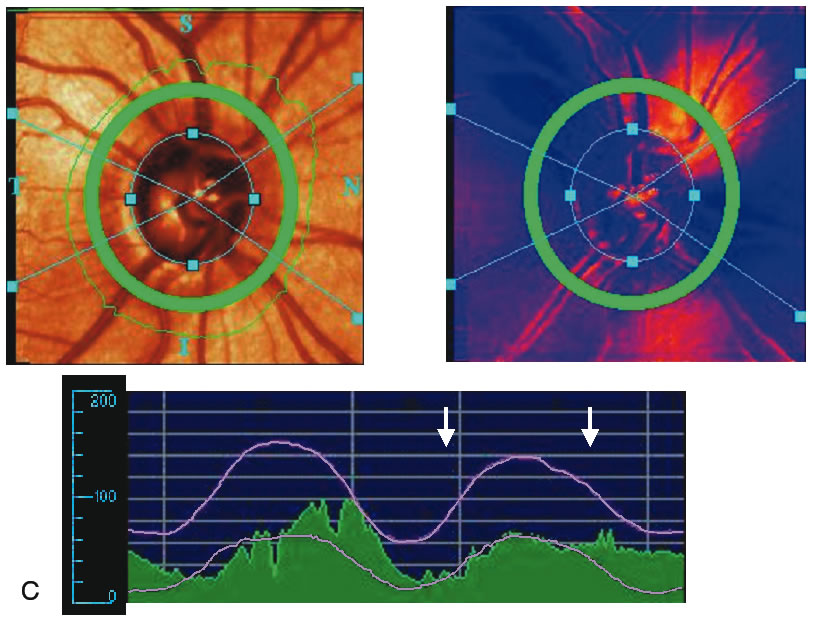

Stereometric parameters of optic nerve head topography are generated relative to the reference plane and include rim area, rim volume, cup area, cup volume, cup-to-disc ratio, mean RNFL thickness, and RNFL cross-sectional area. Parameters independent of the reference plane include mean and maximum cup depth, height variation contour, and cup shape measure (the statistical third moment of the distribution of all cup depth measurements). A characteristic sign in normal discs is the configuration of the contour line height display that demonstrates a double hump pattern corresponding to the thicker distribution of nerve fibers along the superior and inferior poles of the ONH (Fig. 4). Glaucomatous structural damage is characterized by a reduction of parameters that describe rim structures (area, volume) and indicate tissue loss (cup shape measure, cup volume, cup-to-disc ratio, cup steepness). As shown in Figure 5, glaucomatous alterations are typically associated with an asymmetrical or diffuse flattening of the contour line, or localized depressions corresponding to disc notches.